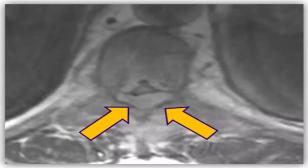

Watch Dr. Anu Amin present “Updates on Management of Spinal Metastases…